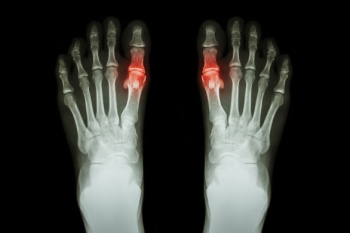

A Guide to Diagnosing Gout

Gout, a form of inflammatory arthritis, can be excruciating, often affecting the big toe and ankles. Recognizing its symptoms is vital for timely management. The diagnosis begins with a keen observation of the symptoms, which are often sudden, intense joint pain, swelling, redness, and warmth, typically striking at night or in the early hours. The affected joint might feel tender to the touch, making even the lightest pressure unbearable. An accurate diagnosis often involves a comprehensive medical history review and a physical examination by a podiatrist. They may also conduct tests like joint fluid analysis to detect urate crystals, which are consistent with gout. Blood tests measuring uric acid levels can aid in confirmation, although high levels do not always guarantee a diagnosis. Imaging tests, such as X-rays, may reveal joint damage in chronic cases. If you have pain in the top of your foot, with a focus on the big toe, it is strongly suggested that you contact a podiatrist who can effectively treat gout.

What Is Gout?

Gout is a type of arthritis caused by a buildup of uric acid in the bloodstream. It often develops in the foot, especially the big toe area, although it can manifest in other parts of the body as well. Gout can make walking and standing very painful and is especially common in diabetics and the obese.

Gout can easily be identified by redness and inflammation of the big toe and the surrounding areas of the foot. Other symptoms include extreme fatigue, joint pain, and running high fevers. Sometimes corticosteroid drugs can be prescribed to treat gout, but the best way to combat this disease is to get more exercise and eat a better diet.